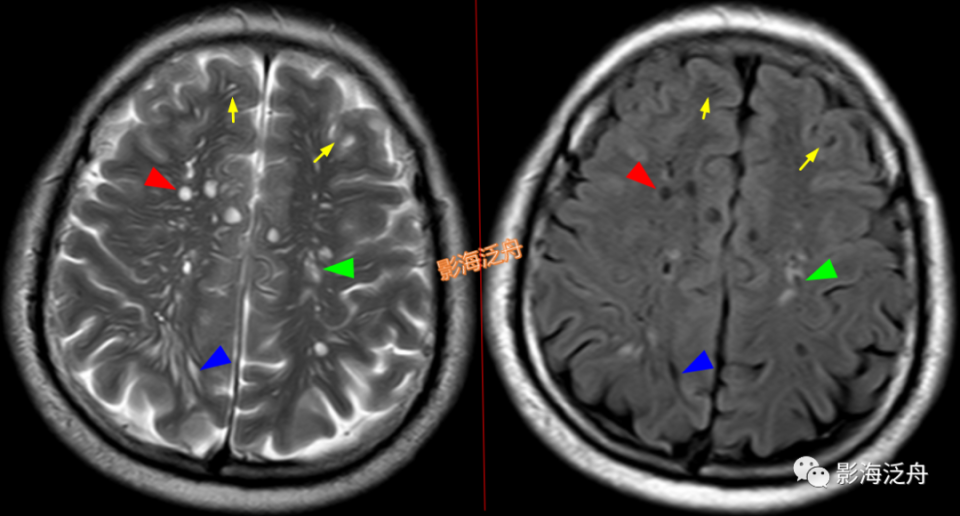

左侧基底节区腔梗灶,病灶既不像类圆形也不像规则的长条状,在Flair序列上灶周可以看到淡淡的高信号影(红箭)。基底节区的腔梗灶位置相较于扩大VR腔隙往往更加靠近上份层面、形态不规则,且随着病程时间延长Flair序列高信号会愈加明显。

左侧基底节区腔梗灶(红箭头),尽管后部的那个病灶看起来有点圆,但在Flair序列病灶周围可以看到非常明显的高信号(绿箭),代表局部胶质增生,证明其为慢性期腔梗灶而非扩大的VR腔隙,其余病变(黄箭)为对称性分布,呈斑点状或长条状,Flair序列灶周无高信号,诊断VR腔隙更为合理。